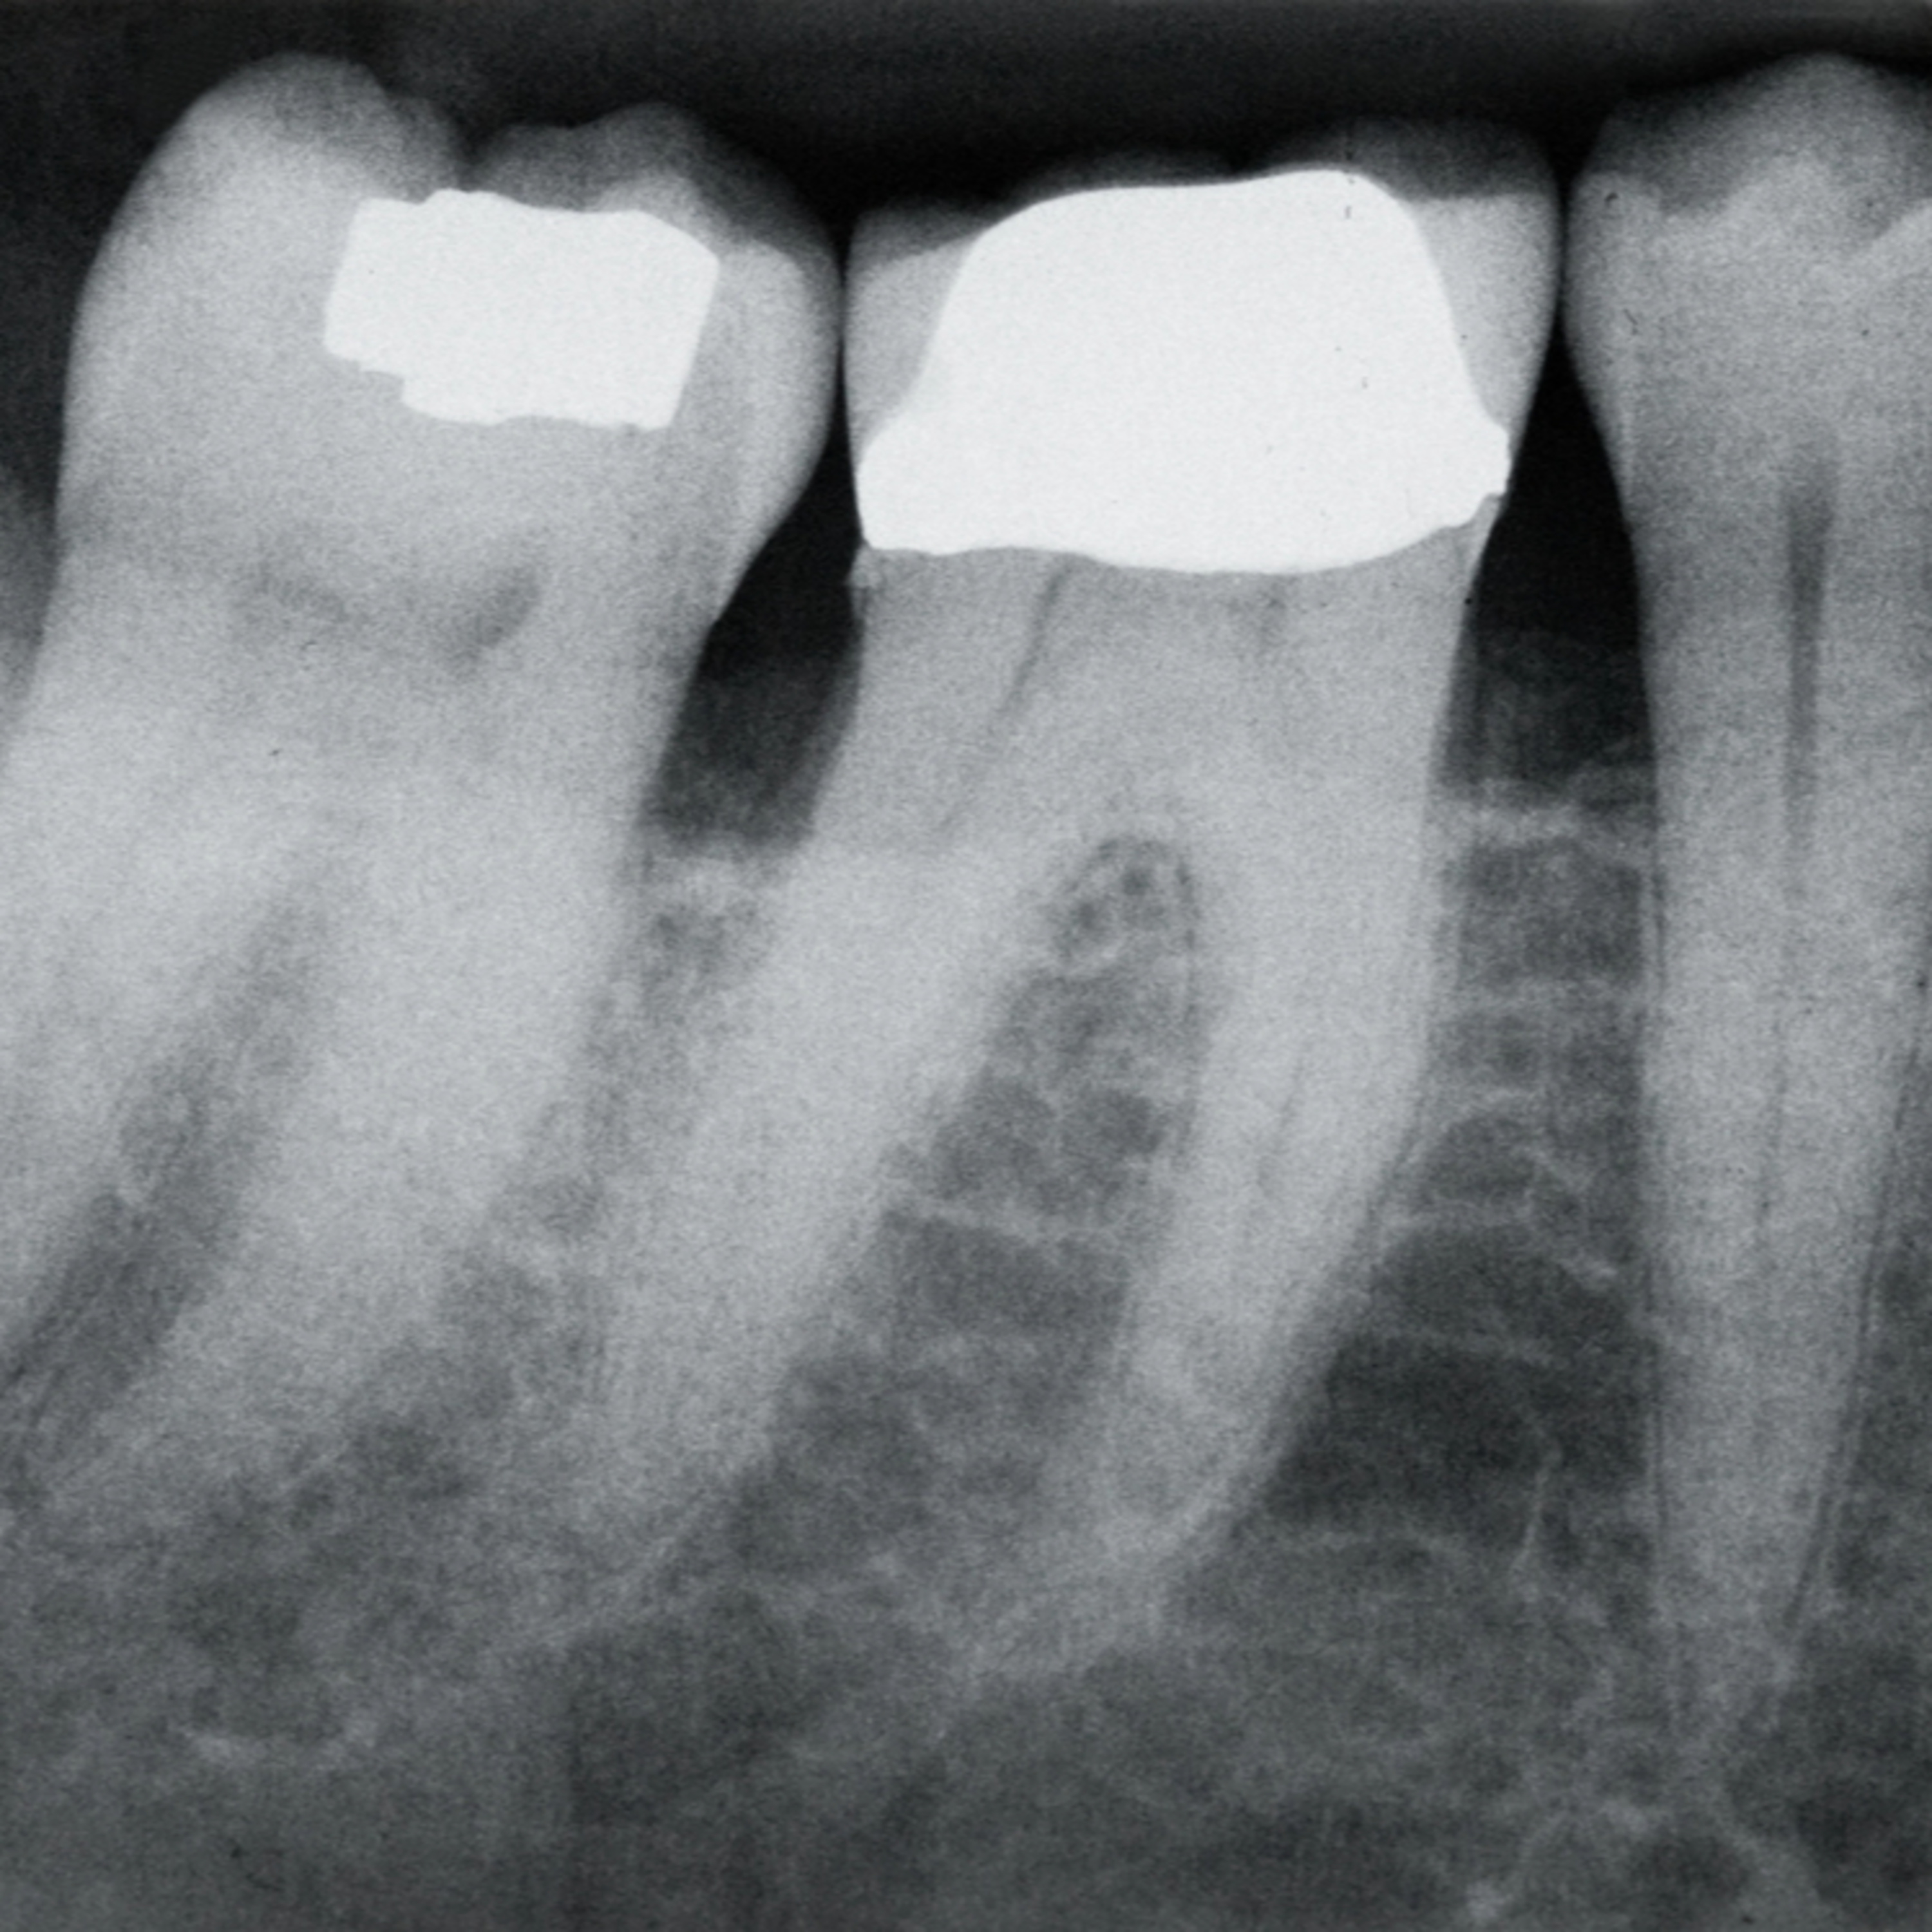

Dental features have been used to estimate age in humans for centuries and may be used with great accuracy in both living and deceased individuals. However, refinement of these techniques to align with modern clinical practice is ongoing. Dr Hosam Alharbi and colleagues at Qassim University in Saudi Arabia have introduced an amended version of an established technique to assess whether dental imaging systems used in modern clinics are suitable for determining human age.